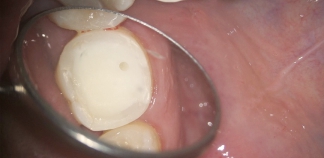

До лечения

Жалоб не было, пришел на осмотр.

Пациенту 40 лет.

Как лечили

Удалены старые реставрации и кариес. Запломбированы корневые каналы гуттаперчей. Установлен стекловолоконный штифт, восстановлен зуб.

Лечение проведено в течение двух недель.